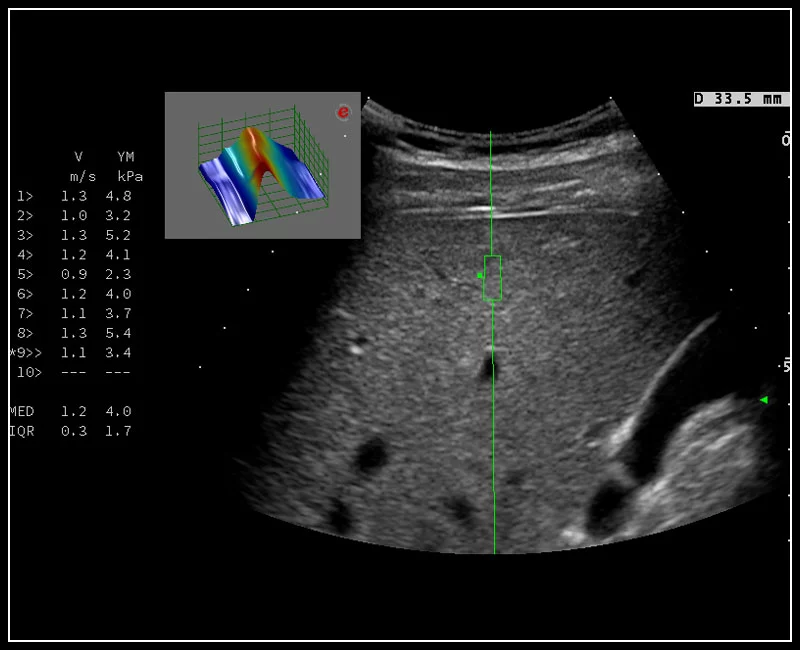

MyLab™9 Platform - QElaXto point Shearwave Elastography in liver

MyLab™9 Platform - QElaXto point Shearwave Elastography in liver